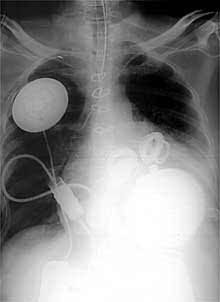

Mejora el paciente al que se le implantó un corazón artificial

El enfermo de 50 años a quien el pasado día 2 se implantó un corazón artificial ha mejorado sensiblemente, según los médicos que le operaron en el Hospital Judío de Louisville (Kentucky, EE UU). Aunque persiste la gravedad del paciente -que arrastra un importante historial de problemas cardiacos y renales-, los facultativos confían en que rebase sobradamente el plazo de un mes de vida que se le concedía antes de la intervención. La operación, a cargo de los cirujanos Laman Gray y Robert Dowling, duró más de siete horas.

El corazón artificial, llamado AbioCor, puede hacer innecesarios muchos trasplantes. Es de plástico, poliuretano y titanio y funciona con una pila eléctrica que bombea las cavidades ventriculares. El aparato sólo se acelera en función de la actividad física del paciente. El AbioCor carece de cables y por tanto no se conecta a ningún motor exterior, lo que proporciona al paciente una gran autonomía.